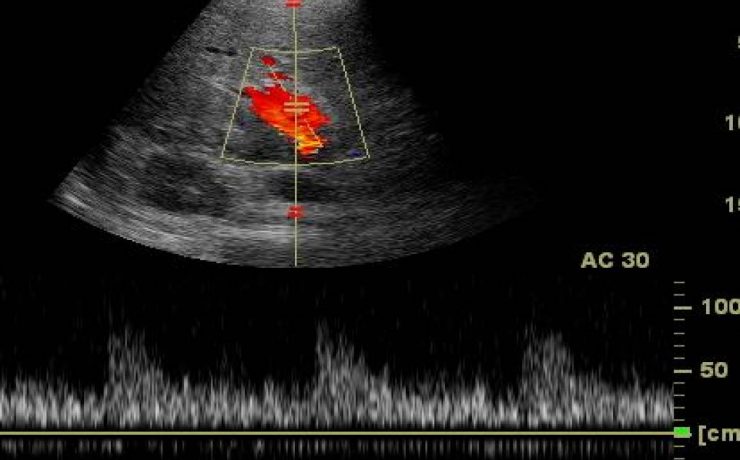

A pesar de la dificultad que conlleva la exploración ecográfica del páncreas, la ecografía abdominal continúa siendo la exploración de elección inicial en los pacientes con sospecha de patología pancreática. Además, aunque la localización retroperitoneal profunda del páncreas dificulta su estudio, los importantes avances técnicos que ha experimentado la ecografía